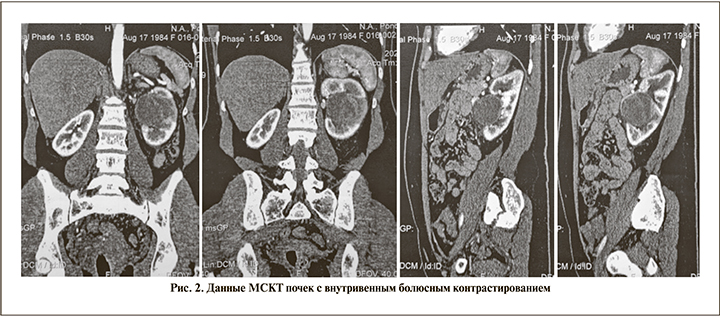

Данные МСКТ почек с болюсным контрастированием от 10.09.2020. Почки расположены обычно. Размер правой почки – 80×45×62 мм, левой – 92×63×68 мм. Контуры левой почки неровные за счет наличия преимущественно в средней трети, по передненаружному контуру образования с включениями мягкотканного компонента с неравномерно выраженными контурами размером до 67×49×51 мм, с выраженным истончением прилежащей паренхимы почки, компрессией синуса почки, с неравномерным накоплением контрастного вещества. В области указанного образования отмечается зона снижения перфузии контрастного вещества с нечеткими контурами (рис. 2).